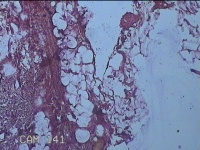

后枕部包块

性别

男

年龄

40岁

临床诊断

头部脂肪瘤

一般病史

发现后枕部包块2年俞,无疼痛基本。

标本名称

大体所见

灰白暗红色包块2.5x2x1.3cm一个,表面光滑,切开包块呈实性,切面灰白淡黄色,质软。